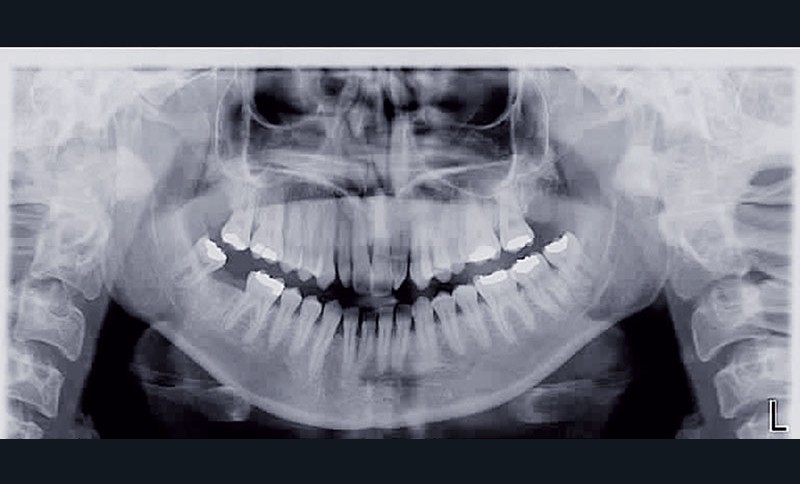

• anomalie de la forme d’arcade maxillaire, 47, 18 et 28 sont absentes. (fig. 1 à 8), 48 est positionnée très postérieurement, quasiment au niveau de la branche montante (fig. 9 et 11).

Après assainissement parodontal, un traitement par expansion maxillaire avec vestibuloversion des incisives supérieures et mésialisation de 48 en lieu et place de 47 a été choisi. Il a été décidé d’extraire 38. Afin de permettre une reconstitution prothétique pour compenser la microdontie de 12 il est prévu de laisser un espace de part et d’autre de celle-ci, équivalent au diamètre mésio-distal de 22 soit 6,5 mm.